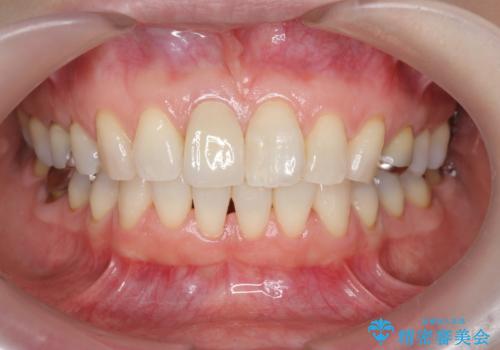

前歯の変色 セラミック審美補綴

- 前歯の変色の改善を希望され来院されました.

以前に神経が死に、根管治療を行った歯の変色が認められたためセラミックによる審美補綴治療を計画します。